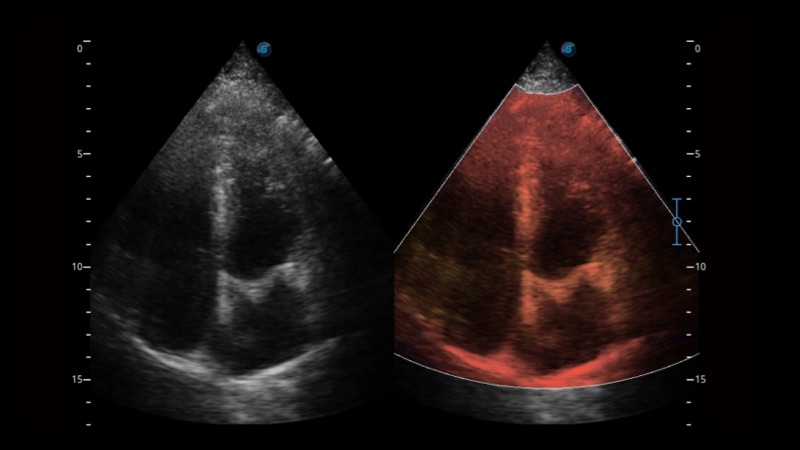

相控阵探头

凭借公海贵宾会员检测中心医疗先进的成像技术和优异的探头技术提供的清晰的图像表现,您可以更自信地做出临床决策。